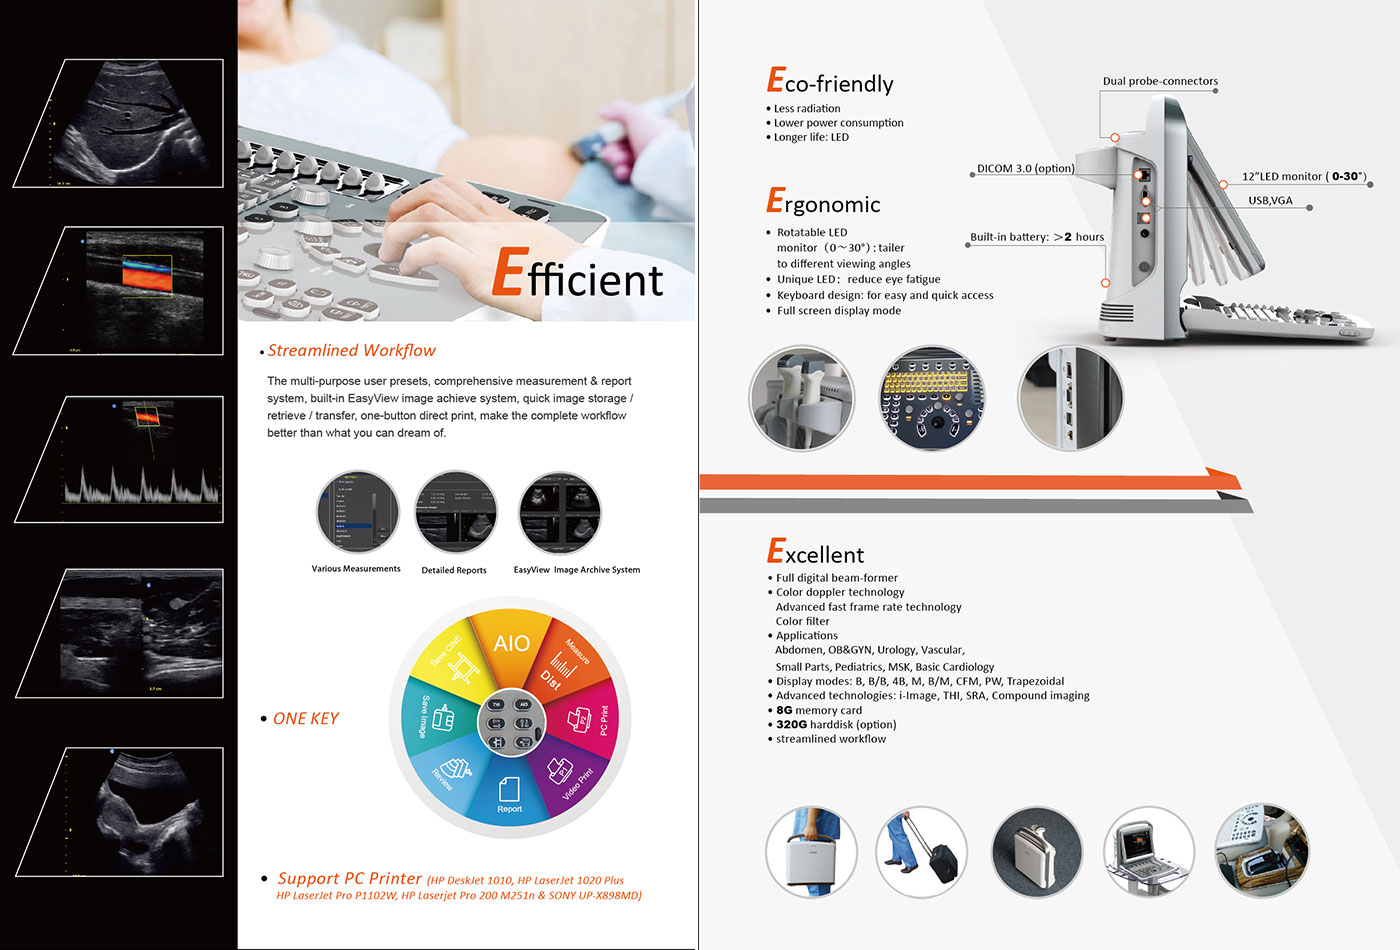

●Less radiation

●Lower power consumption

●Longer life: LED

●Rotatable LED monitor (0~ 30*) : tailer to different viewing angles

●Unique LED: reduce eye fatigue

●Keyboard design: for easy and quick access

●Full screen display mode

●Full digital beam-former

●Color doppler technology

Advanced fast frame rate technology

Color fiter

●Applications

Abdomen, OB&GYN, Urology, Vascular,

Small Parts, Pediatrics, MSK, Basic Cardiology

●Display modes: B, B/B, 4B, M, B/M, CFM, PW, Trapezoidal

●Advanced technologies: i-lmage, THI, SRA,Compound imaging

●8G memory card

●320G harddisk (option)

●streamlined workflow